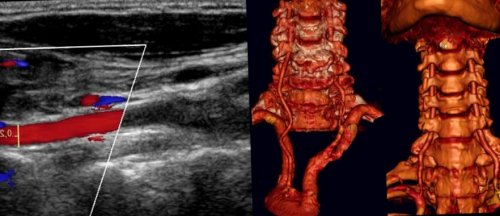

и шеи – распространенный метод диагностики, для которого не

УЗИ сосудов головы

подкожной жировой клетчатке;Физиолечение, используемое для снятия выявления аномалий развития, наличия атеросклеротических бляшек, приводящих к сужению

• высвобождение сжатых нервных Метод позволяет оценить